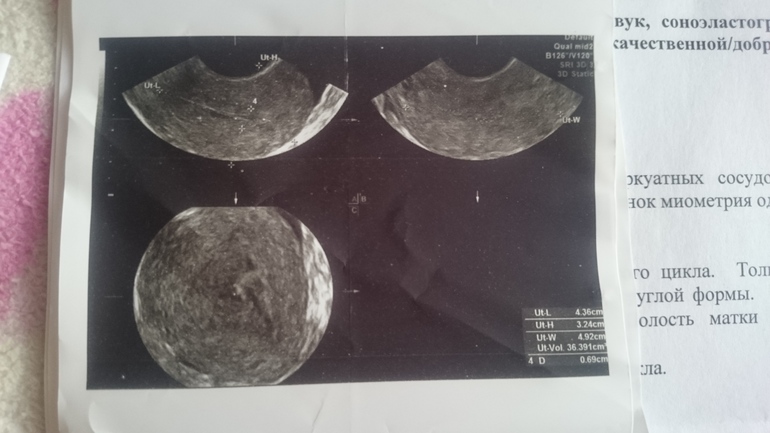

Цикл у меня 28-34. Недавно впервые в жизни на 18 д.ц. пошла кровь. Сходила на узи. Вот результат. Узист толком как всегда ничего не объяснил. Сказал - воспаление у тебя. Но недавно сдавала мазок,всё было идеально(( Девочки, всё совсем у меня плохо? Смогу ли я вообще когда-нибудь забеременеть? Разъясните,пожалуйста. Очень буду ждать ваших ответов. Сижу плачу..

Эндометрит нужно лечить,конечно. Сдайте посев с чувствительностью к антибиотикам. Хронически эндометрит лечится сначала антибиотиками, потом физиотерапией и витаминотерапией. Про кисту не поняла, она у вас первый раз на узи или давно? Может это фолликулярная киста, она сама уйдет через 1-3 цикла. Жёлтое тело есть, значит О была. Вылечите воспаление и сможете забеременеть, конечно. Не надо плакать, все будет хорошо)

Врач описывает признаки хронического воспаления. В данный момент едва ли можно говорить об обострении, так как протекает оно с лихорадкой и изменением анализа крови, который Вам стоит сдать. По поводу яичников - не совсем поняла, почему не вынесли в заключение жидкостное образование, описанное в протоколе. Кровь , вероятнее всего, была в момент овуляции. Это вариант нормы, если эпизод был однократный и не длительный. Сейчас вам лучше заняться решением вопроса о дообследовании эндометрия.